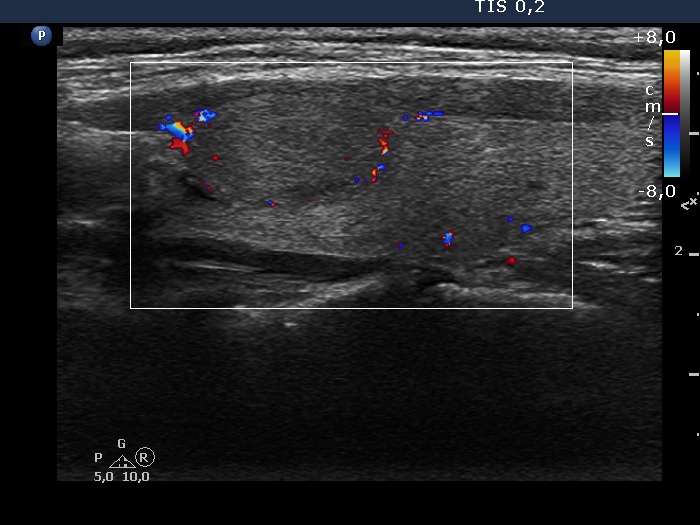

Intranodular hyperechogenic figures - case 270 (ultrasonographic picture 5)

Left lobe, longitudinal view, color Doppler mode. The nodule presents signs of perinodular blood flow.